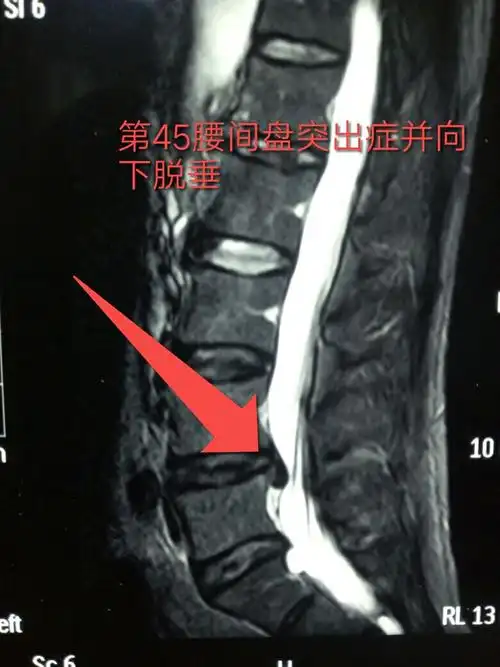

特巨大游离性脱出腰间盘突出症

核磁共振显示突出并想下脱垂的椎间盘组织

外院mr:椎间盘髓核脱出向上游离